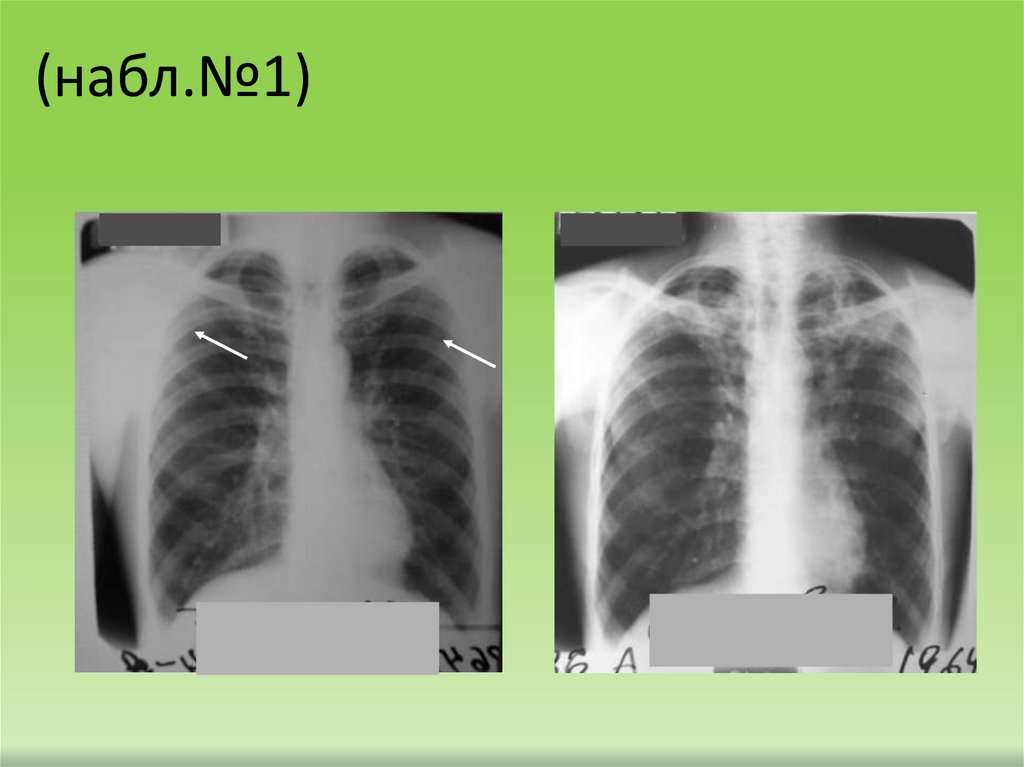

(набл.№1)